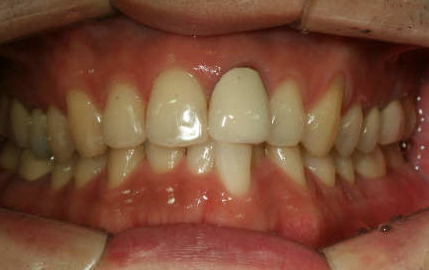

예쁘게 교정하고 마무리 유지장치까지 붙였습니다.

일반적으로 비발치교정의 경우 발치교정보다는 적은 시간인 1년에서 1년반 정도의 시간이 걸립니다.